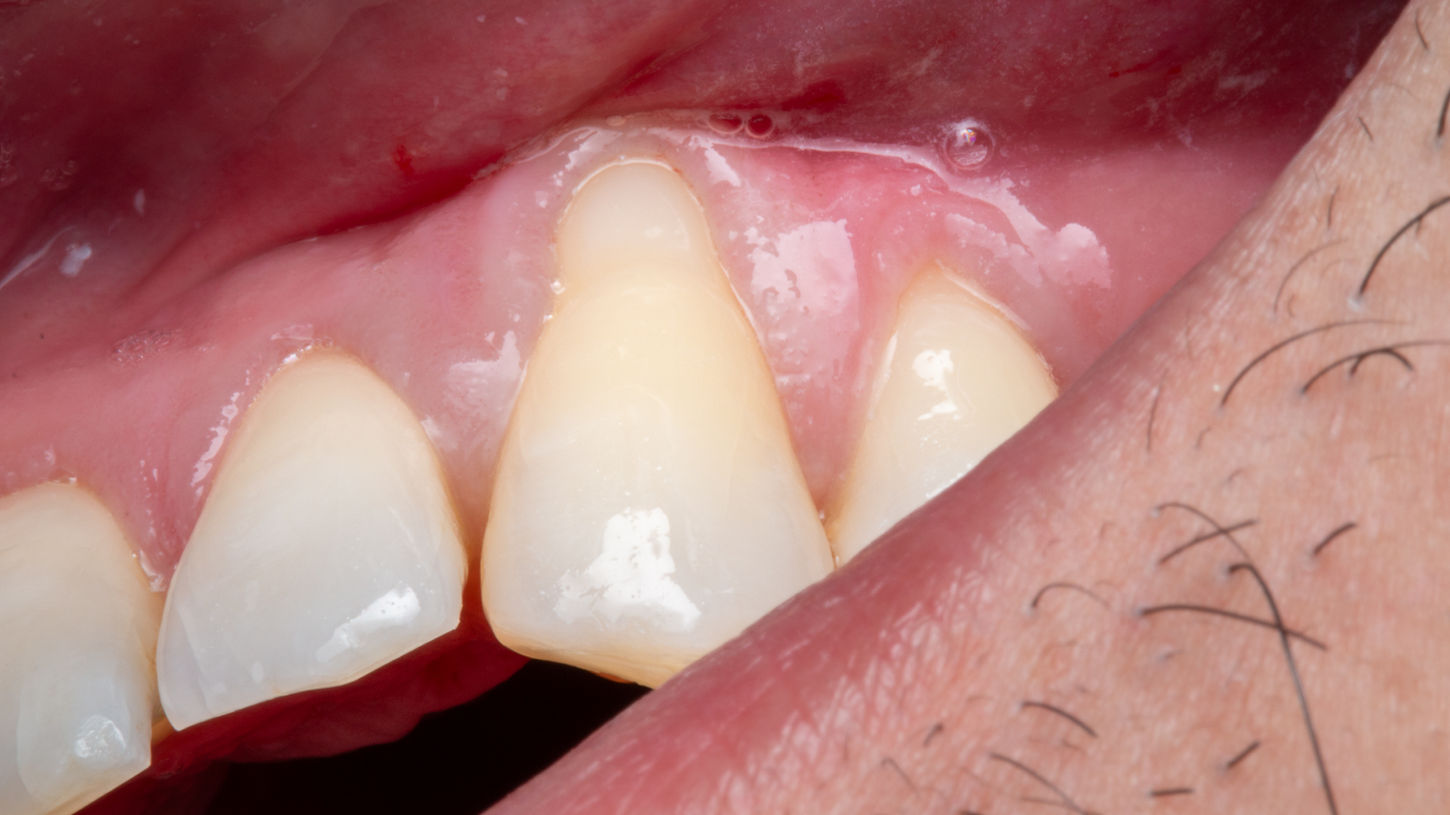

This gingival graft case at SOL Dental Arts in Maspeth, Queens addresses recession around a canine tooth with soft tissue treatment designed to improve root protection, reduce sensitivity concerns, and enhance gumline appearance. When gum recession exposes the root surface, the issue can be both functional and cosmetic. A grafting procedure may be recommended to strengthen the area, improve tissue coverage, and create a more stable, natural-looking gum contour. This type of case is especially important when the patient wants to address recession early and protect long-term periodontal health while also improving smile esthetics.

Root coverage and gumline contour improvement

Follow-up healing assessment